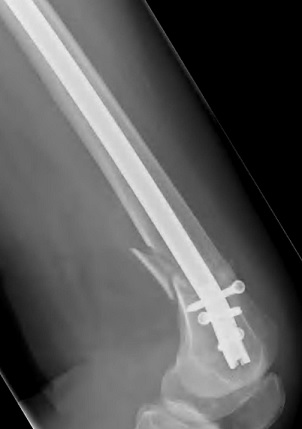

Retrograde Intramedullary (IM) nails are best suited to extra-articular supracondylar DFFs, particularly transverse or short oblique patterns (Figure 2). IM nails allow percutaneous insertion, reducing soft-tissue disruption, and load-sharing biomechanics favour faster rehabilitation. However, knee pain is a recognised complication and requires active physiotherapy to prevent it from developing. Contemporary data from comparative studies show that IM nails achieve outcomes equal to or superior to plating in many DFFs, particularly in frail patients with intact articular surfaces. This evidence supports the growing preference for IM nailing in these high-risk cohorts.

Radiograph of a left retrograde intramedullary nail fixation, lateral view Figure 2: Radiograph of a left retrograde intramedullary nail fixation, lateral view [19].